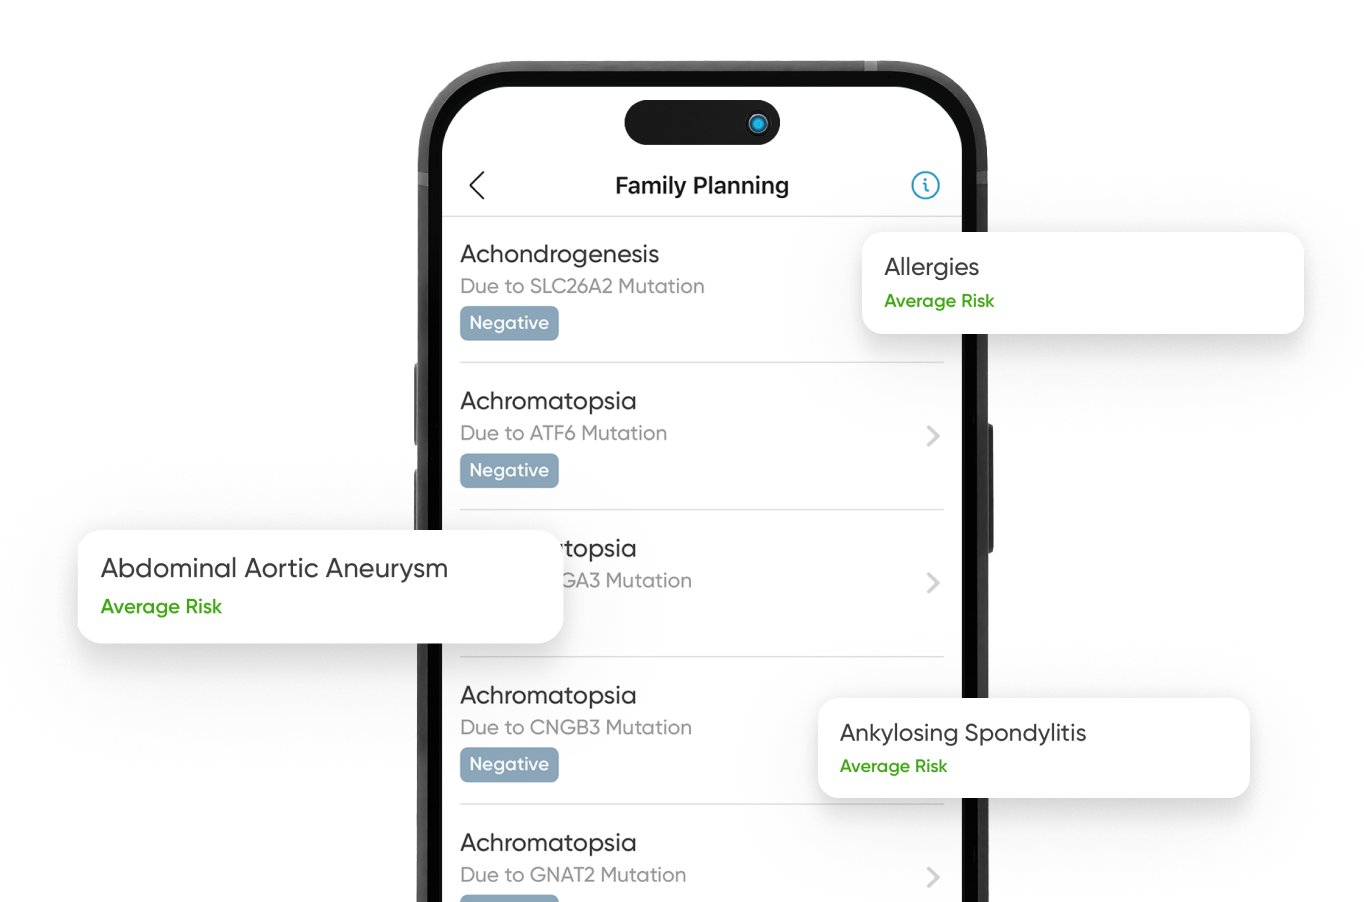

Plan a healthier future for your children with DNA-driven insights. Understand key genetic markers and hereditary risks, to safeguard your children’s health.

The CircleDNA test offers a comprehensive analysis of your genetic makeup, providing valuable insights into various aspects of your health and well-being. This test covers a wide range of areas, including genetic predispositions to certain health conditions, traits related to nutrition and fitness, and carrier status for inherited diseases. Additionally, it provides personalized skincare recommendations, dietary guidance, and ancestry information.

For example, the test can reveal sensitivities to different food groups, enabling you to make more informed dietary choices. It also estimates your lifetime genetic risk of developing certain disorders, offering a thorough overview of potential health risks.